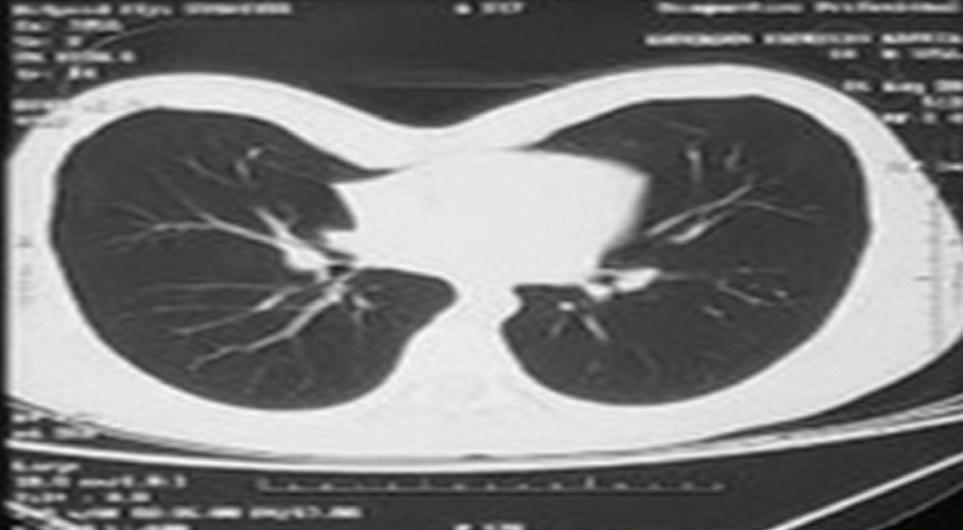

Se solicita tomografía torácica en el cual se evidencia compresión de estructuras mediastinales y un índice de Haller de 4.0 según la división del diámetro transverso entre el anteroposterior del tórax (Foto 2). El ecocardiograma reporta compresión y desplazamiento cardiaco, con volumen fracción de eyección normal. Con lo que se toma la decisión de llevar a sala de operaciones.